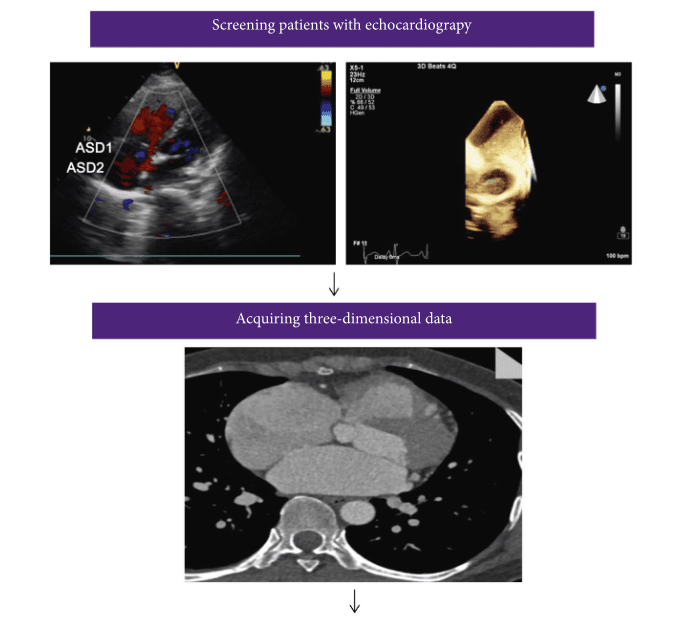

Simple working flowchart in patients with multiple ASDs, from image acquisition to 3D printed solid and hollow model.

62 patients diagnosed by TTE with two or more ASDs with a 5mm or more diameter, were enrolled in their non-randomized study for analysis. 30 had cardiac computed tomography angiography (CTA) ahead of surgery in order to get data to create their 3D printed heart models. The CTA images were reconstructed and saved in DICOM format, before being imported to Materialise Mimics software. Cardiac masks were generated for 3D models, and 3-matic software was used to hollow them. The STL files were 3D printed, in hollow fashion, at 1:1 scale on a ProJet MJP 2500 Plus 3D printer out of silicone.